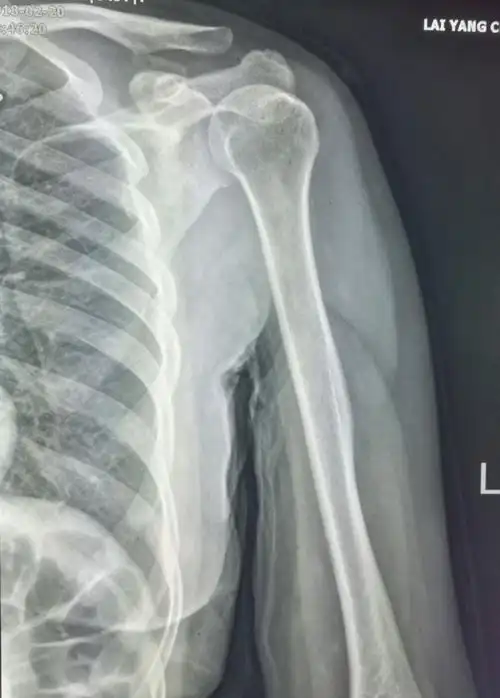

肩关节正常正位片

肩部背部外伤要注意肩胛骨,肩关节正位不宜观察,可以结合斜位,最好ct

肩关节x线检查体位大全